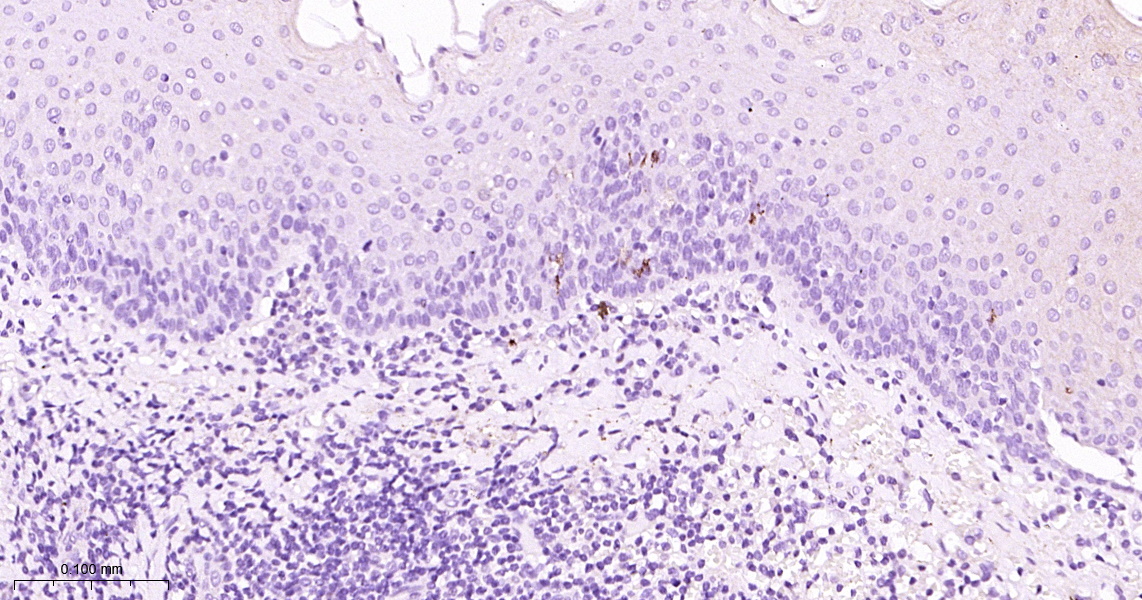

• IHC-P

IHC-P IHC-P1:100-500